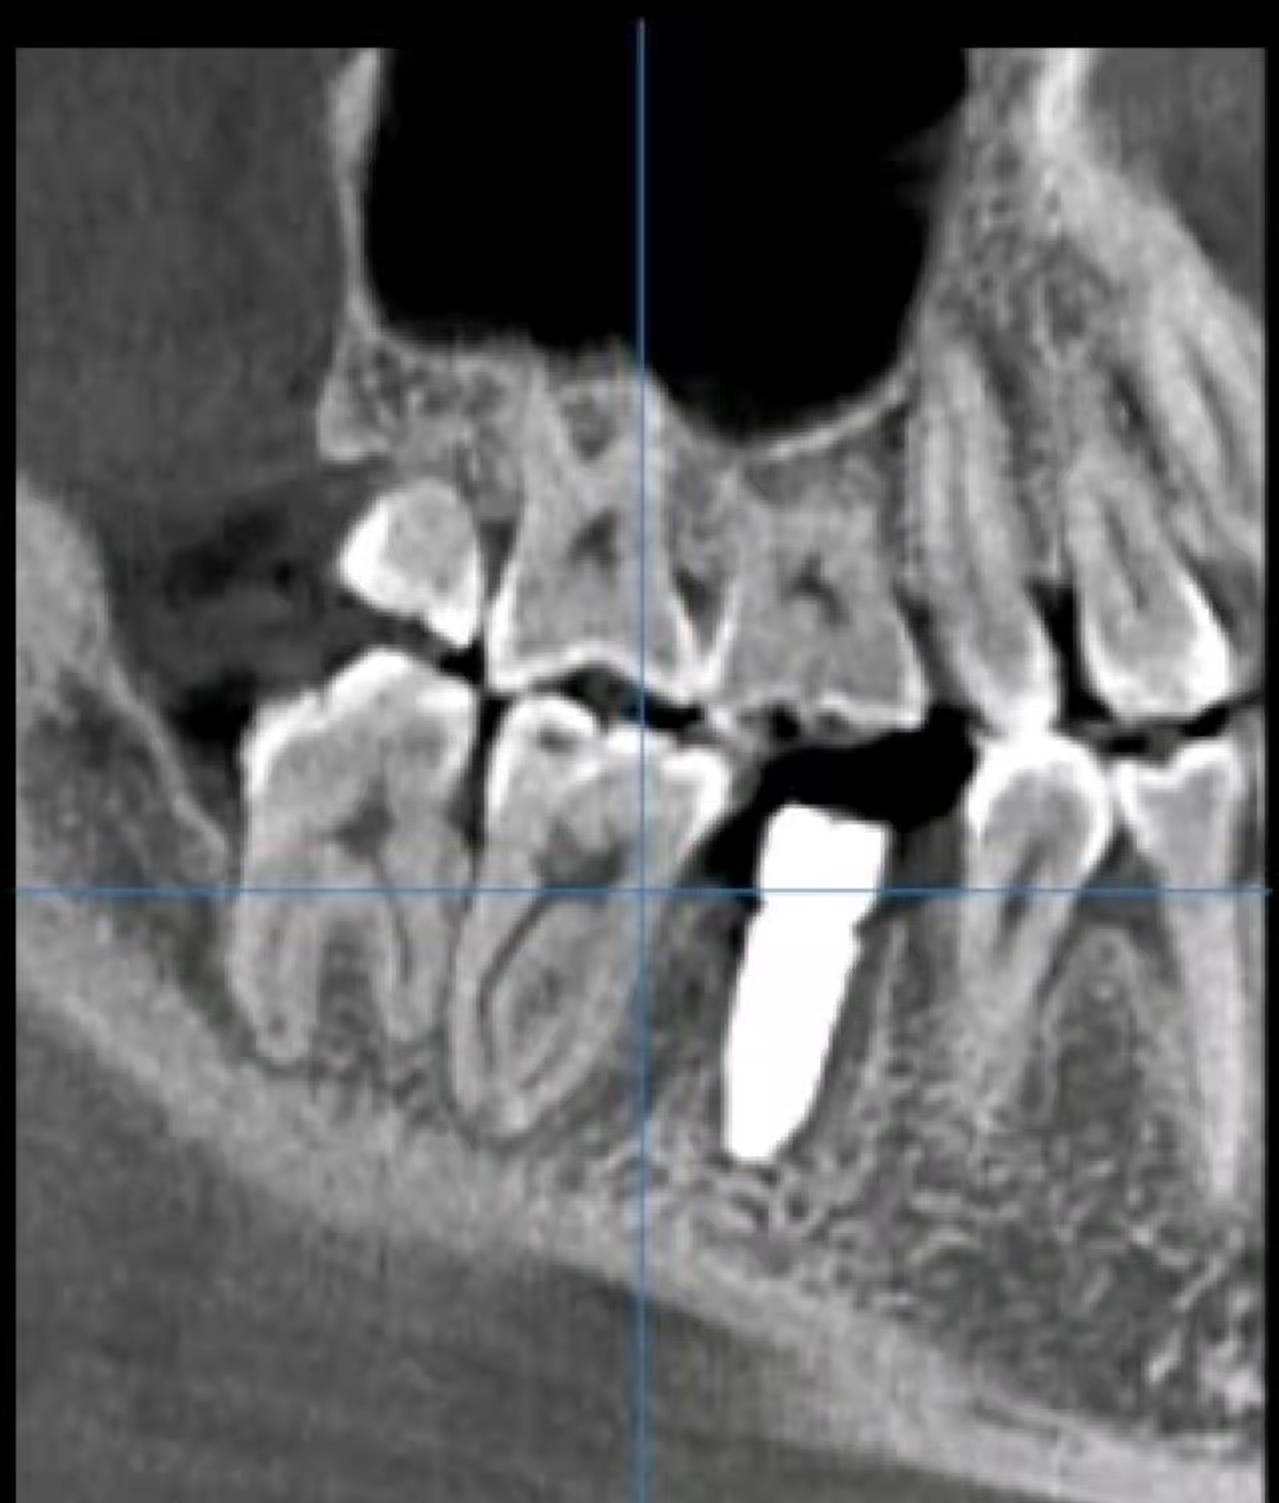

術(shù)后CBCT圖: